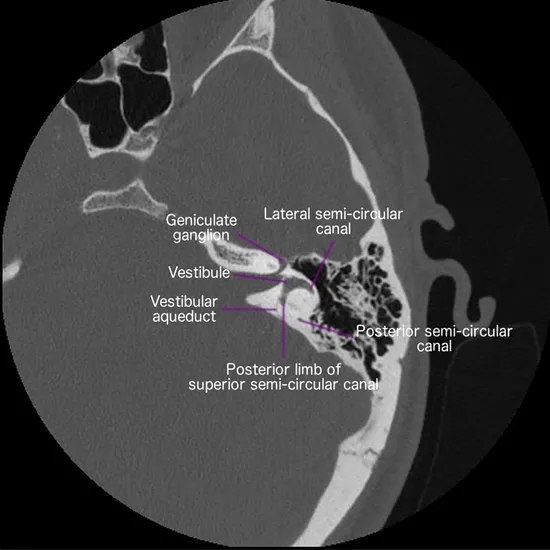

CT (Computed Tomography) inner ear coronal is an imaging scan used to obtain cross-section images of the bony structures within the inner ear at the coronal plain. This scan is recommended to identify the problems within the inner ear.